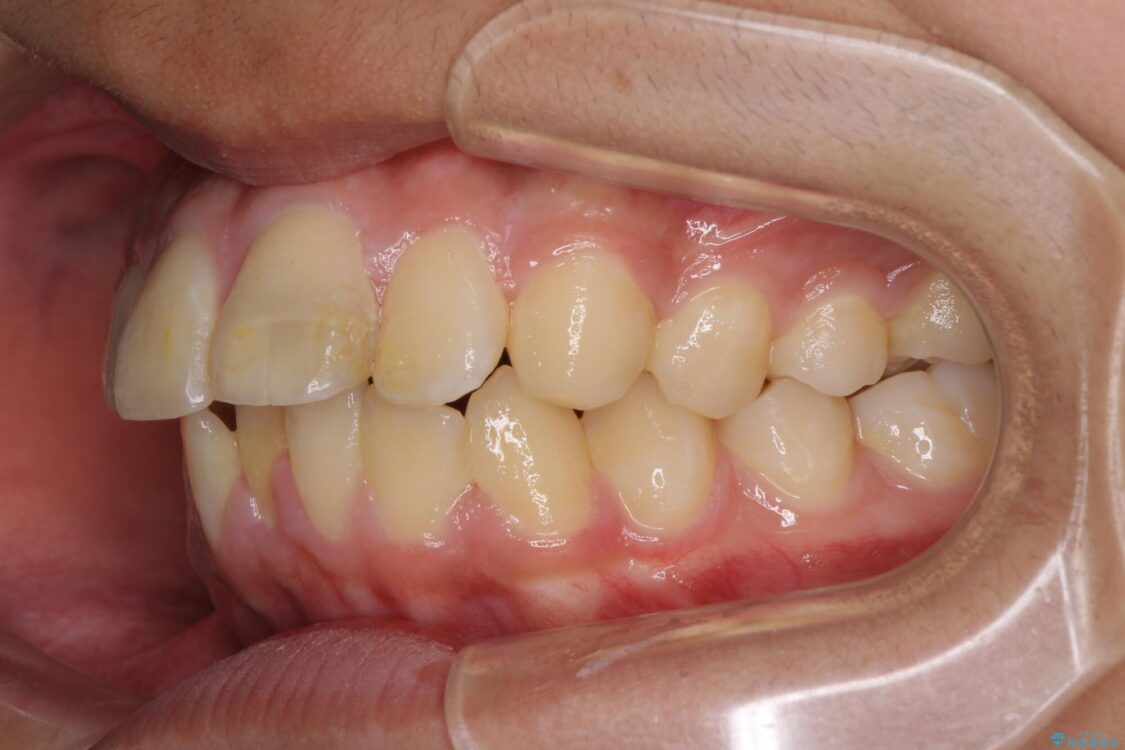

治療途中

• 膨らんだ口元 ワイヤー装置での抜歯矯正 治療途中画像